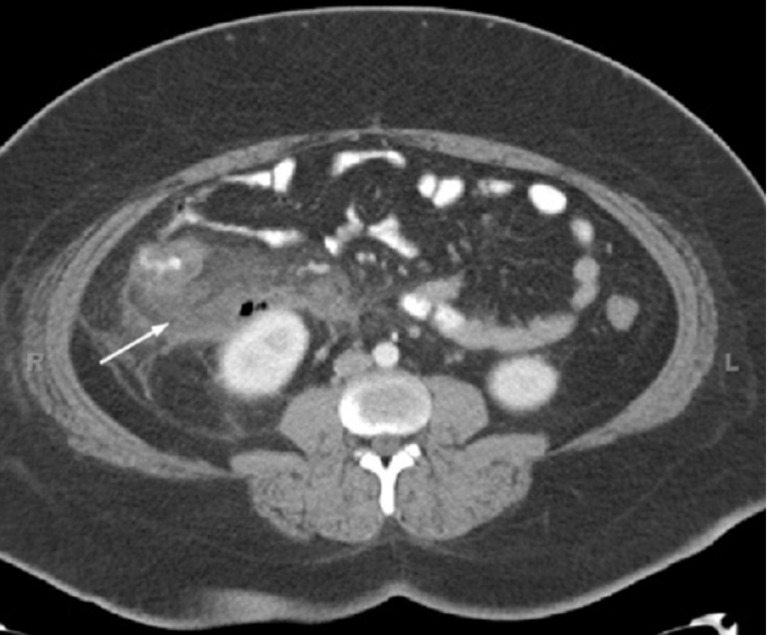

Ct Scan For Abdominal Pain . Abdominal ct scans are used when a doctor suspects something might be wrong in the abdominal area but can’t find enough information through a physical exam or lab. Ct scans can detect a pancreatic lesion or a large gastrointestinal mass, but a normal ‘standard’ protocol ct scan (that is,. A good physician history and physical exam are. Acute cholecystitis, pancreatic abscess, pancreatitis, alcoholic liver disease, or blockage of bile ducts can be diagnosed through abdominal. It can help diagnose abdominal problems, such as. A ct scan of the abdomen is one component of the workup of abdominal pain. Computed tomography (ct) is recommended for evaluating right or left lower quadrant pain. Axial (a) and coronal (b) views reveal diffuse mural and periappendiceal edema, with thickening of the appendix (red arrows).